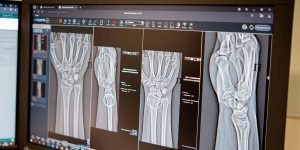

Алгоритмы автоматически идентифицируют поврежденные участки и проводят необходимые измерения, даже при наличии нескольких переломов одновременно. Сегодня московские рентгенологи располагают более чем 60 ИИ-сервисами. Некоторые из них позволяют отличить норму от патологии, другие, например, измеряют границы и размеры аномалий. Эти сервисы применяются в 43 клинических направлениях, добавила вице-мэр Москвы.

По словам главного внештатного специалиста по лучевой и инструментальной диагностике Москвы Юрия Васильева, повреждения предплечья, кисти и голени встречаются довольно часто. Процедура выявления перелома включает осмотр врача-травматолога с последующим рентгенологическим исследованием. Специалисты применяют ИИ-алгоритм как ресурс, способный повысить точность и скорость анализа лучевого изображения, что играет решающую роль в установлении диагноза.